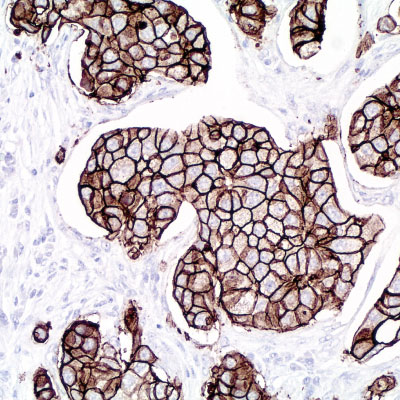

Immunohistochemistry integrates a set of methodologies that use antibodies as specific reagents capable of identifying and establishing specific links with tissue constituents that function as antigens.

Established bindings can be visualized under microscopic observation, due to the labeling of antibodies that cause color development whenever antigen-antibody complexes are formed.

​Vitro Turkey Diagnostics, through its exclusive representation of Master Diagnostica in Turkey, sells antibodies and equipment for immunohistochemical diagnosis (IHC), offering a wide panel of primary antibodies (more than 300 references), as well as universal and high-quality detection systems. sensitivity, based on micropolymer technology for in vitro diagnostics.

With the main objective of providing innovative and top quality antibodies for immunohistochemical diagnosis, we work daily to be informed of the problems and needs of the market, in order to be able to offer our customers the most innovative antibodies with total quality assurance.

Top quality antibodies for immunohistochemical diagnosis. More than 300 references.

Universal and high-quality detection systems. Sensitivity, based on micropolymer technology for in vitro diagnostics.